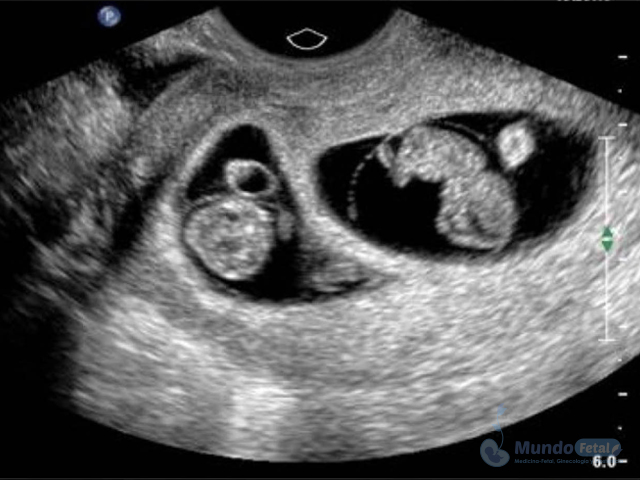

Ultrasonido Embarazo Múltiple

Es esencial detectarlo desde el primer trimestre (especialmente 11-13.6 semanas de gestación) con la intención de conocer el número de bebes, cuántas placentas y bolsas amnióticas, ya que el seguimiento de estos es distinto, esto por los riesgos que conllevan de presentar alguna alteración propia de estos embarazos, indicativos de una vigilancia estrecha y estudios complementarios, durante toda la gestación.

• Valorar el bienestar de los bebes, de acuerdo a su evolución en relación al tipo de embarazo.

• Descartar o confirmar oportunamente riesgos y anomalías, sugerentes de vigilancia y estudios complementarios.